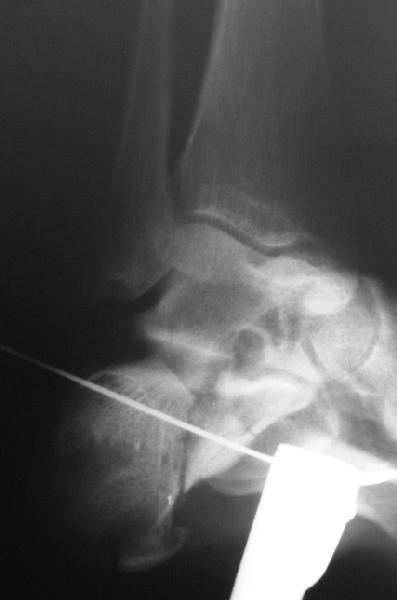

представляю снимки пациента с переломом пяточной кости. послеоперационный снимок этапный - по снятии швов спицы удаляю и наладываю циркулярную гипсовую повязку. к сожалению снимки с удаленной скобой представить не могу но поверьте на слово - консолидация полная, коррекция стойкая.

при планировании операции и ее исполнении выполнена костная аутопластика трансплантатом с гребня подвздошной кости причем трансплантат брался фрезой размером несколько болишим чем образованный в результате травмы дефект. скоба в данном случае обеспечивает компрессию между отломками-трансплантатом